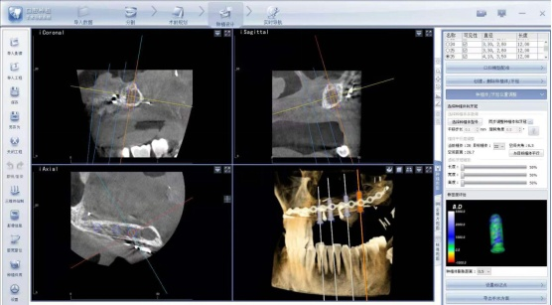

術(shù)中導(dǎo)航屏幕界面

口腔種植手術(shù)導(dǎo)航系統(tǒng)利用對三維醫(yī)學(xué)影像的虛擬可視化,通過拍攝CBCT,進(jìn)行數(shù)據(jù)處理,醫(yī)生通過數(shù)據(jù)分析做出手術(shù)方案,并且在手術(shù)過程中可以實(shí)時(shí)追蹤,降低了手術(shù)的風(fēng)險(xiǎn),縮短了手術(shù)的治療時(shí)間,是頜骨患者的福音。